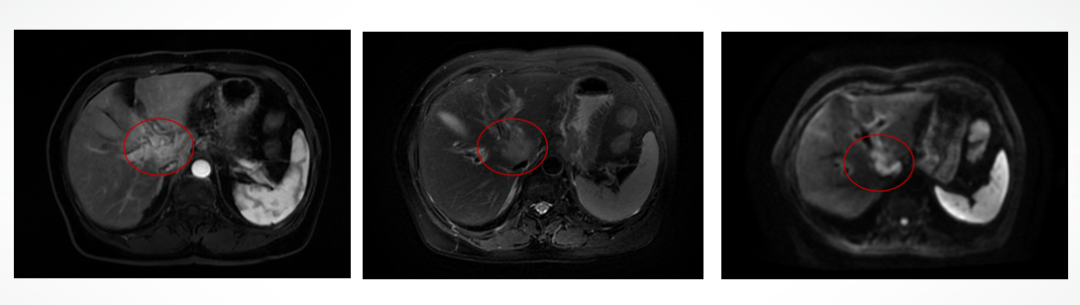

2023年10月肝转移灶进展,2023-10-19开始行T-DXd靶向治疗。疗效评估:肝转移灶PR,骨转移灶SD。

肝转移灶疗效评估:PR

骨转移灶疗效评估:SD

2025-9-9 MRI示:肝多发转移瘤化疗后复查,对比前片(2025-06-11)肝内病变进展,腹膜后淋巴结增大。